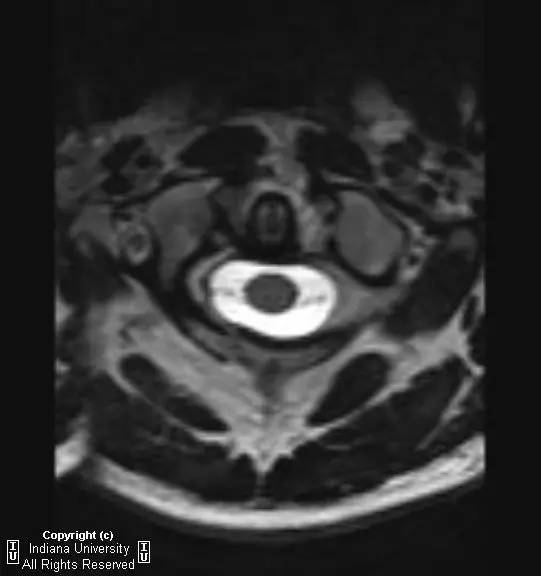

CR: C1侧块相对C2侧块外侧移位约5 – 6 mm,符合Jefferson骨折。椎体周围软组织明显肿胀。MR: 椎体周围间隙可见血肿。覆膜完整。寰枕前韧带断裂。寰枢前韧带完整。左侧横韧带从C1侧块的内侧分离,CT对应在C1侧块内侧见小撕脱骨折。翼状韧带完整。寰枕后韧带完整。前纵韧带和后纵韧带完整。黄韧带完整。

Jefferson骨折(Jefferson fracture)是前后弓均累及的C1环粉碎性骨折。Jefferson骨折为头顶受打击并轴向载荷的结果,力从颅骨经枕骨髁传递到颈椎,C1侧块在枕骨髁和C2上关节面之间被压缩,基于侧块的形状产生向心力而导致C1爆裂骨折。齿状突开口位或冠状位重建CT图像应仔细观察双侧C1和C2关节侧块间有无偏移。虽然C1侧块相对C2上关节面侧方移位提示存在骨折,但在X线片上有时难以发现骨折线。MR可显示相应的韧带损伤。

Jefferson骨折。A,侧位片示C1后弓骨折线(箭)。B,开口位示C1侧块相对于C2偏移(箭)。C和D,轴位CT图像示骨折线通过C1环前、后部(箭)。E,冠状位CT图像示翼状韧带小的撕脱骨折(黑箭)。此图像上也标注了C1在C2上方偏移(白箭)。